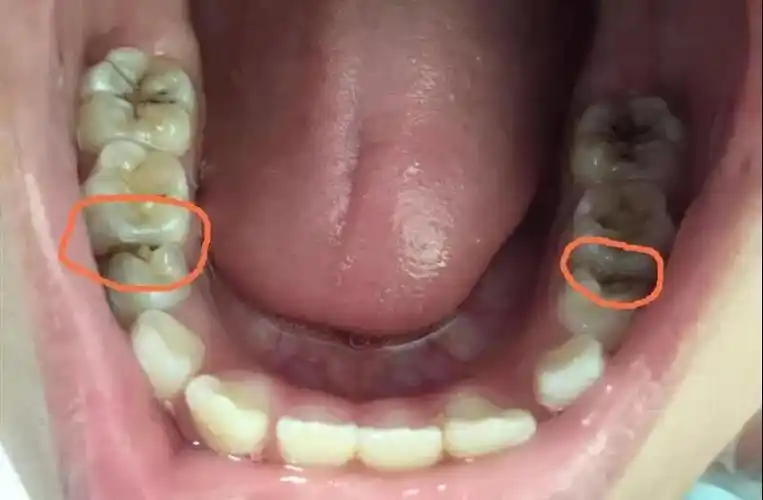

术前诊断门牙龋洞,一开始很小,工作太忙没有及时治疗_圈子-新氧美容

前牙邻面龋损修复1例

去除"隐患"——治疗邻面龋

邻面龋坏,隐性龋,如不及时发现,就真的一眼看上去影响美观了!

病例分享前牙邻面龋的治疗技巧